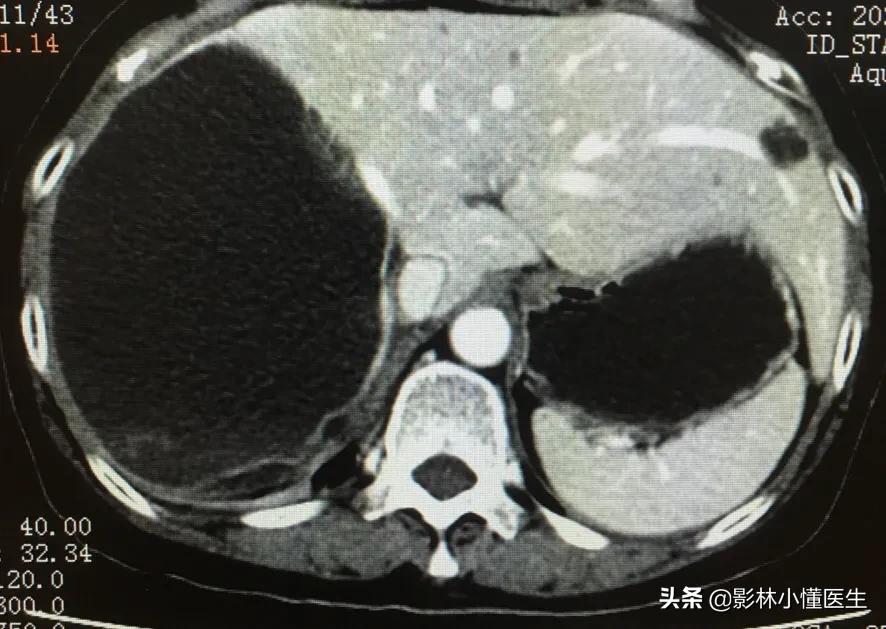

囊肿较大,约10cm局部伴出血、破裂。